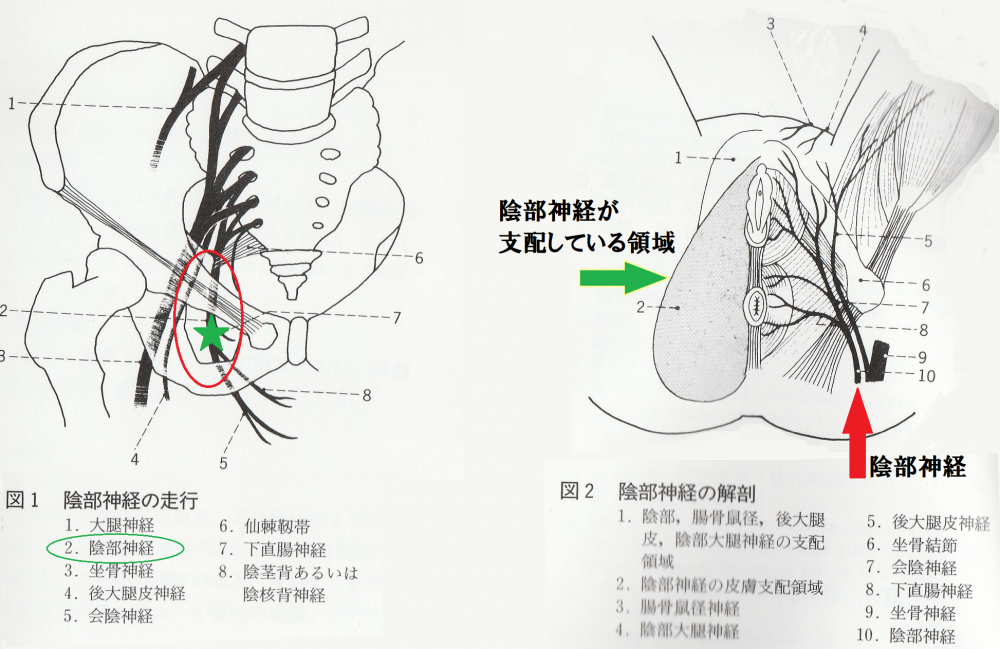

慢性前立腺炎 慢性骨盤痛症候群には陰部神経刺鍼が必須です 名古屋市緑区 はり 灸 マッサージ 指圧 ライフ治療院